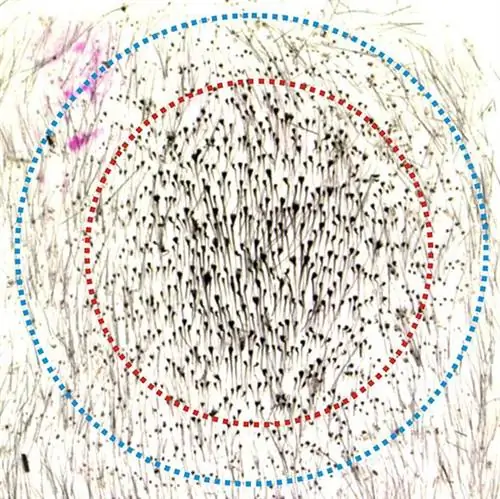

Chih-Chiang Chen из Университета Южной Калифорнии и его коллеги испытали необычное лекарство от этой проблемы: выдергивание волос. Для своего исследования они выщипывали 200 волосков на спинах мышей по определенной схеме - в одном подходе всего по несколько на область, а в другом - в более плотной последовательности, при которой все выщипанные волоски исходили из круглой области всего пять миллиметров. по размеру.

Результат был ошеломляющим: там, где на маленьком участке было вырвано много волос, вскоре после этого отрастали волосы - и значительно больше, чем было выдернуто раньше. Исследователи насчитали от 450 до 1300 новых волосков на крошечном участке и в непосредственной близости от него.